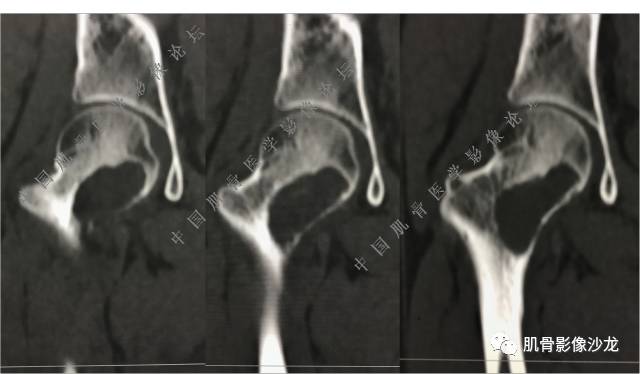

主诉:右侧股骨近端持续疼痛1月余

现病史:1个月前因天气转冷突然右侧股骨疼痛,无乏力麻木,遂就诊于当地医院X线检查发现右股骨异常密度,为进一步诊治来我院。

既往史:高血压史。余无特殊。